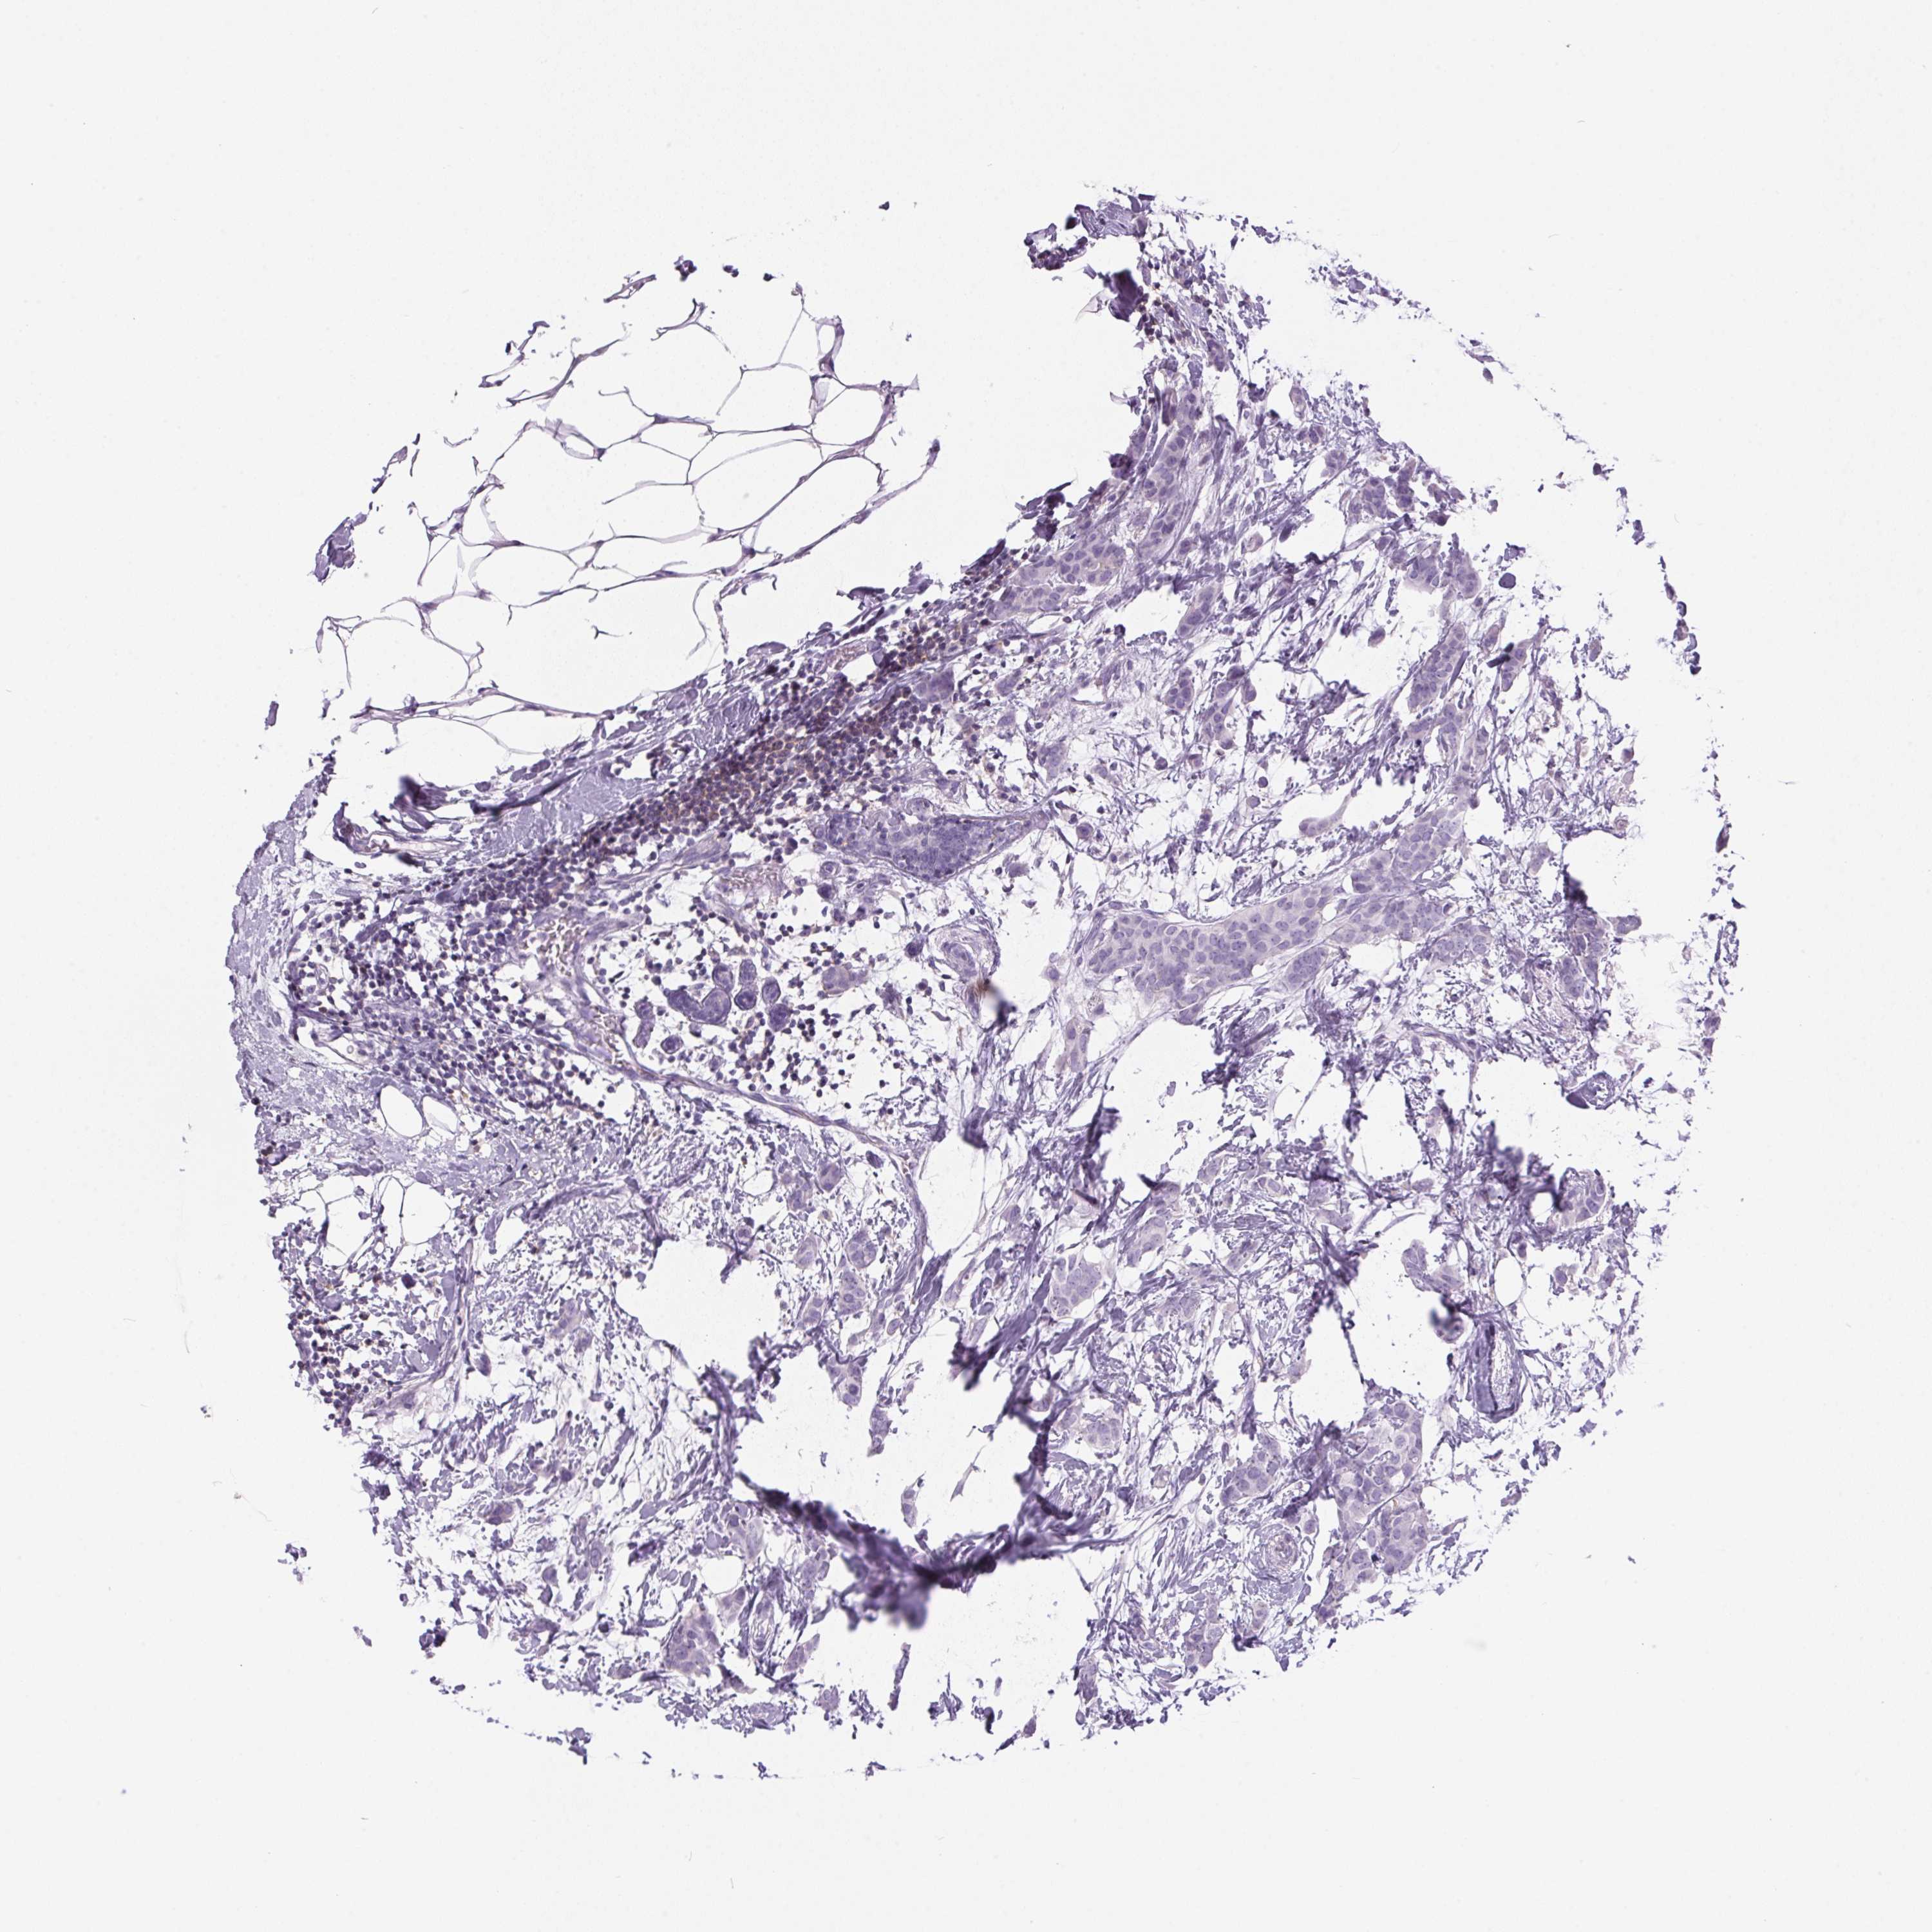

CANCER BREAST CANCER Show tissue menu

BRCA TCGA BRCA VALIDATION PROTEIN EXPRESSION

ANTIBODIES

AND

VALIDATION